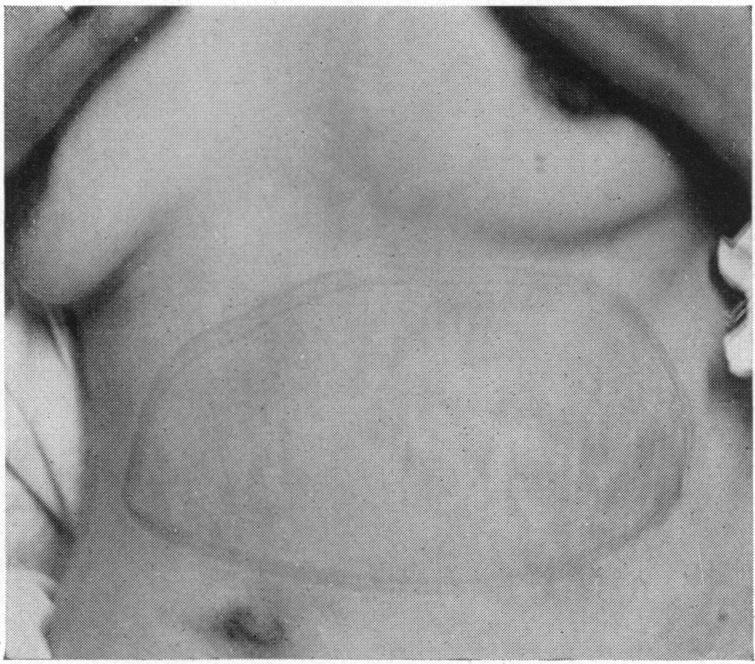

CAVERNOUS ANGIOMA OF THE SPLEEN.

CYSTIC DISEASE OF THE SPLEEN.